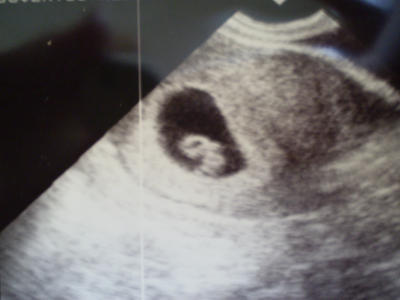

Pandus! Nagyon szép a kis Pandafiacskád!